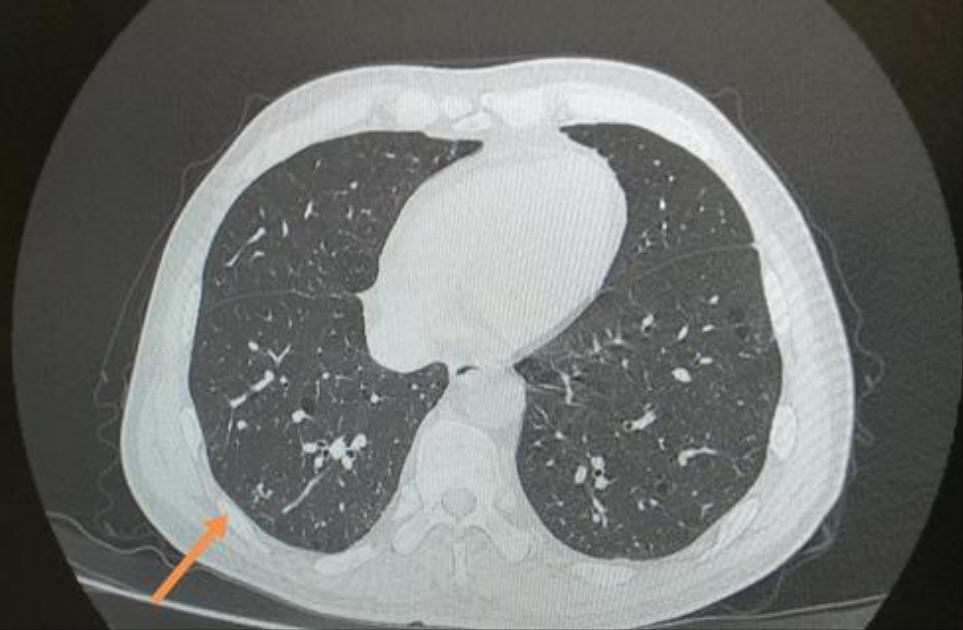

我重发下图片,您再帮我看下,帮我定下性质和严重程度,年过了,如需手术,准备找家医院尽快做了。

下面是这次检查的CT报告和图片(这次医院不给刻光盘了,在门诊医生电脑上拍照的)。